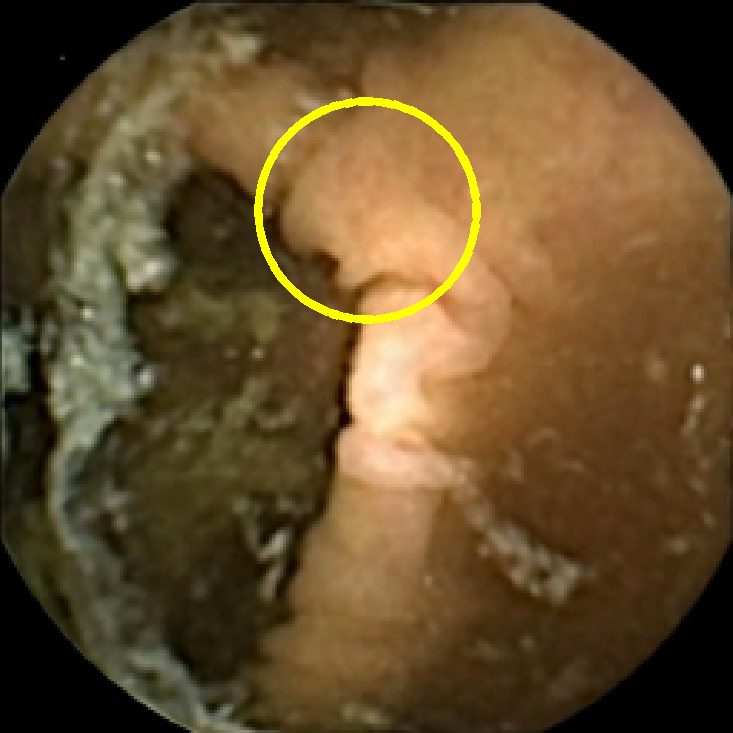

The examples of incorrect classification of frames are presented in Figure 6. The first two examples show false negatives, each highlighting a possible source of classification error. The example in column (a) shows the case where the feature corresponding to the polyp was too stretched out and thus was rejected by the eccentricity criterion (21). In contrast, the feature corresponding to the polyp in column (b) has passed the combined geometric criterion (22), but the radius was below the threshold of the binary classifier. Examples in columns (c) and (d) show the two sources of possible false positives. The false positive detection in column (c) is due to insufficient illumination correction. The bright spot is not fully corrected at the pre-processing stage and subsequently generates a polyp-like feature in the mid-pass filtered frame that happens to pass through all the criteria. Finally, in column (d) a mucosal fold is classified as polyp. Note that such cases are the most difficult to deal with, as the mucosal folds can often be hard to distinguish from polyps even for a human operator.